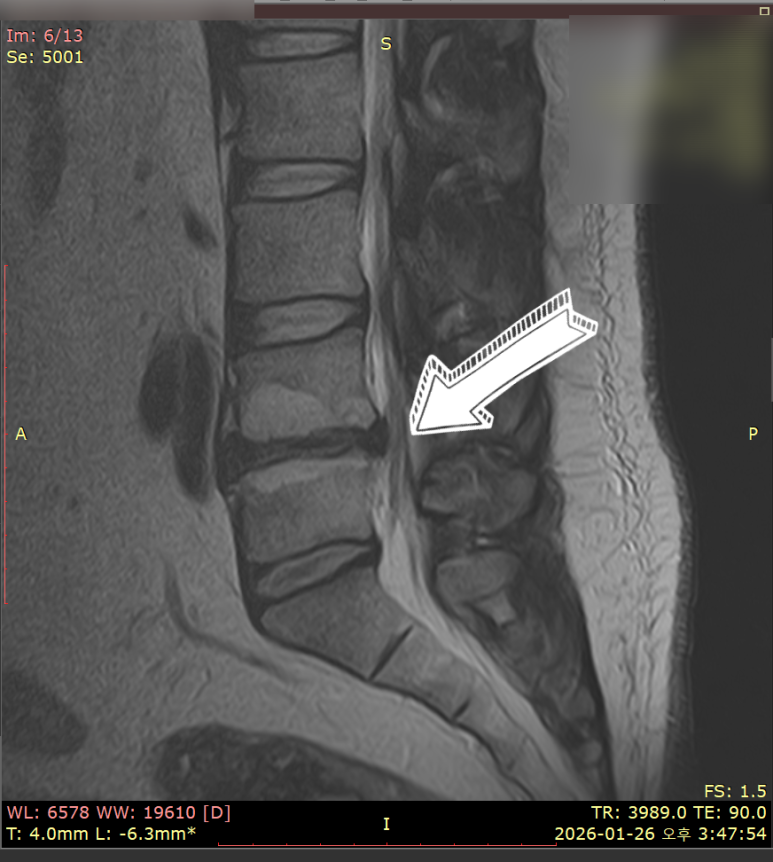

예를 들어 L4−L5 사이 디스크가 문제라면,

한의사는 허리 L4 극돌기 뼈 정중앙을

손으로 고정합니다.

이후 테이블 하단부가 천천히 내려가면서

특정 허리 분절(L4−L5)만 집중적으로 벌어지죠.

3주 이상 만성 허리 통증, 방사통이 지속될 경우

MRI 검사와 근전도 검사가 필요하고요.

MRI 검사 소견을 토대로

한의학의 신수(腎兪), 대장수(大腸兪),

그리고 화타협척혈(華陀夾脊穴) 부위를

경혈 초음파로 확인하면서

문제가 있는 병변 부위를 찾아냅니다.